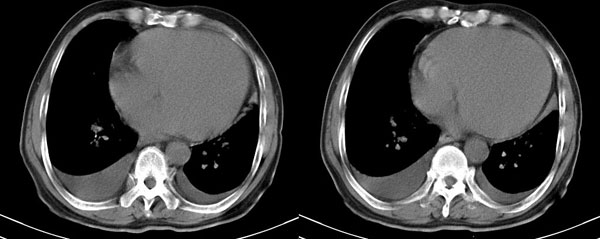

男性,68岁,心慌、胸闷五年,加重半个月

pe:双肺呼吸音粗,右下肺呼吸间减弱,叩诊呈浊音,双肺未闻及干湿性罗音,心界向左下扩大,律不齐,可闻及早搏,心尖区可闻及3/6级sm。实验室检查缺如

右肺下叶肺野密度增加,呈毛玻璃样密度改变,右恻叶间胸膜有增厚,双恻胸腔有积液.肺内改变我首先考虑是肺泡性肺水肿.

右下肺团块状影疑肺隔离症,另单从影像学角度考虑双侧胸水,以右侧明显,结合病史心源性胸水可能性大。

心衰致双侧胸腔积液,右肺下叶肺水肿,腹水。

1.胸腔积液合并右肺下叶含气不良.

2.左心室增大.